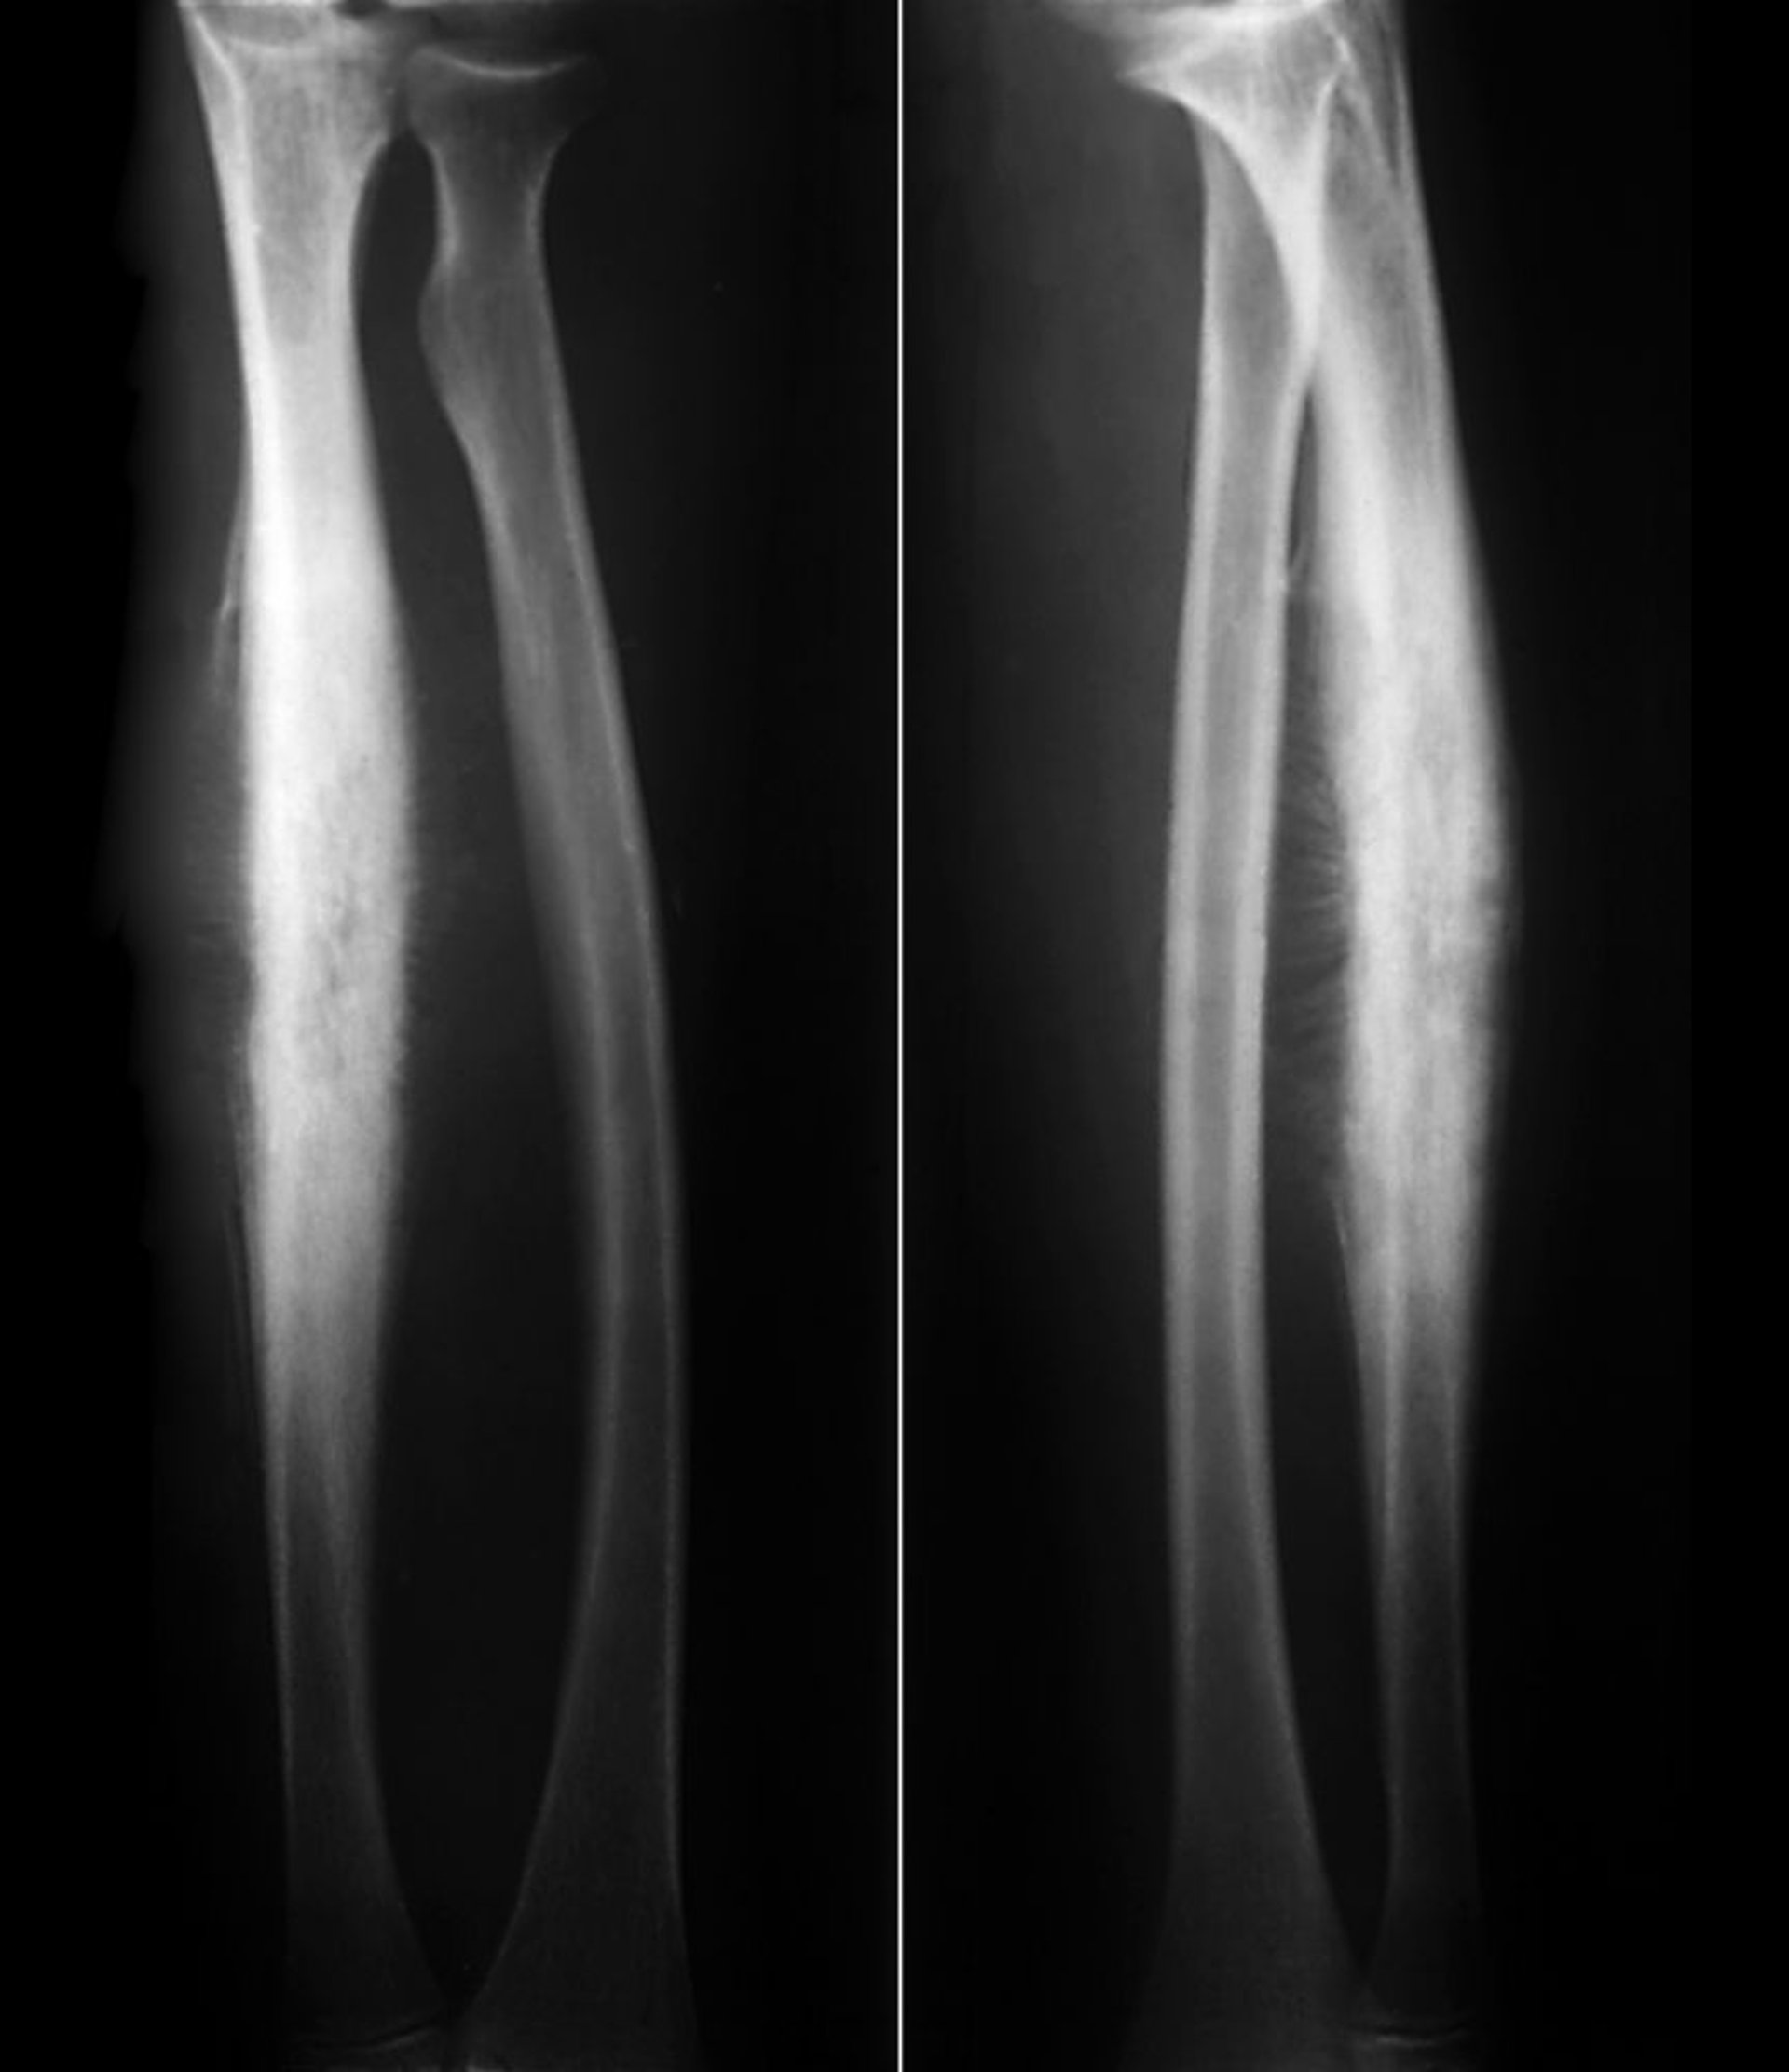

Sarcome d'Ewing du radius

Ce sarcome d'Ewing de la diaphyse radiale montre une formation osseuse réactive sous-périostée dans une réaction périostée classique en "rayon de soleil" ainsi qu'une destruction lytique de l'os cortical.

ZEPHYR/SCIENCE PHOTO LIBRARY